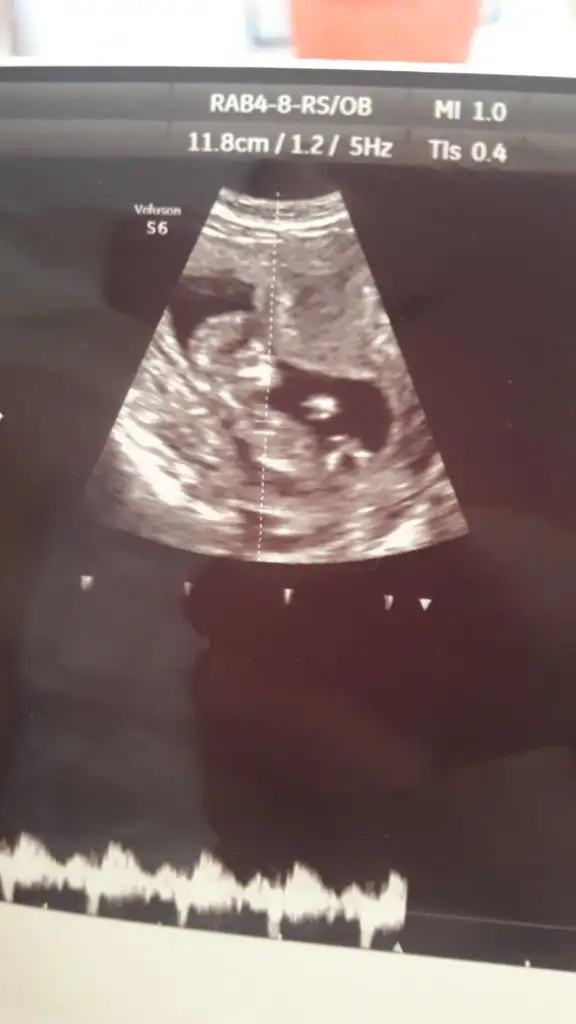

Kizlar bu gecen haftaki usg miz. Cinsiyet icin yorum yapabilir misiniz? 12+4 tu o zaman

Eklentiler

• IMG-20190708-WA0006.webp

18,8 KB · Görüntüleme: 40

• IMG-20190708-WA0008.webp

14,1 KB · Görüntüleme: 45